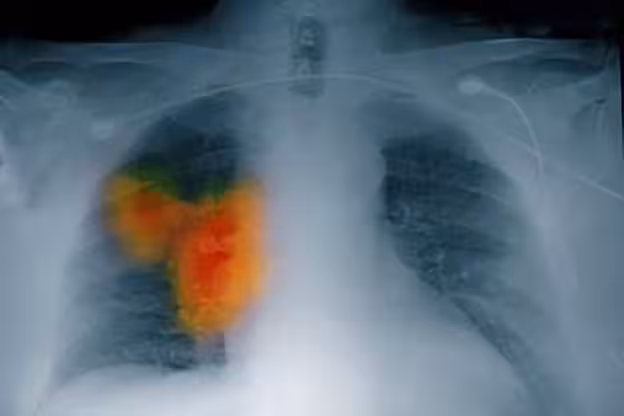

58歲女子確診肺癌,強忍淚水坦言:手部早出現了問題,沒有多重視!

當李阿姨第一次見到醫生時,她仔仔細細地把自己的症狀說了個遍,還提到這段時間為了搞清楚身體狀況,她沒少研究各類健康知識。

在詳細詢問了李阿姨的生活和飲食習慣後,醫生突然拋出一個看似和腹瀉八竿子打不著的問題:「您的手有沒有什麼不一樣的感覺?

比如說麻木、疼,或者使不上勁?」李阿姨一下子愣住了,腦海里像閃電划過一般,突然想起來自己的手確實有點不對勁。

可之前她一直覺得,自己年紀大了,平時又總整理書籍,有點手部勞損很正常,壓根沒往別的地方想。